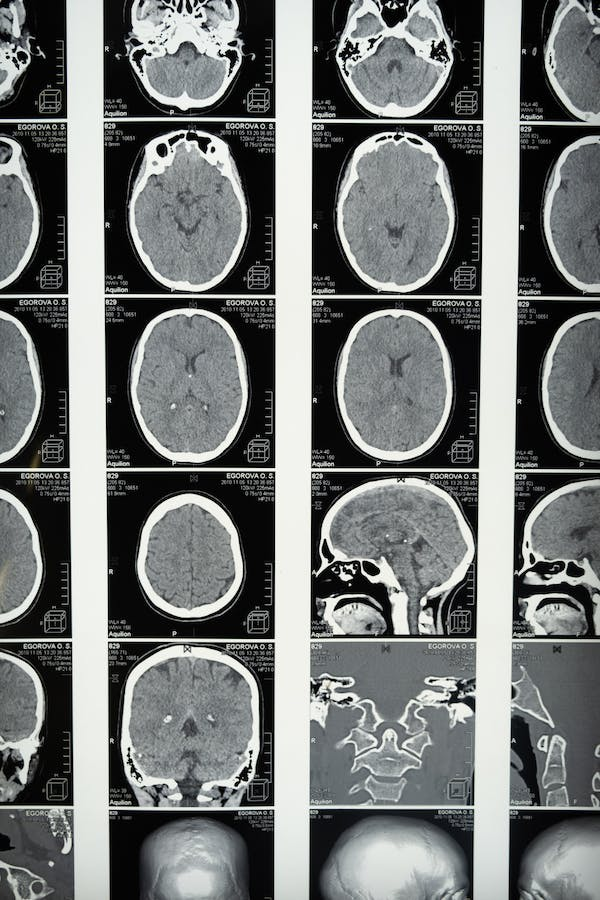

Mirando en el cerebro

Principalmente, la característica más común en la tomografía computarizada cerebral específicas (TC) para la encefalitis por varicela es hipodensidad en los lóbulos temporales que, en ocasiones, afecta también al lóbulo frontal. Además, los ganglios basales suelen permanecer intactos. En el caso de la resonancia magnética (RM), los hallazgos típicos para esta afección son cambios edematosos con hipodensidad en los lóbulos temporales y lóbulos frontales inferiores, mientras que los ganglios basales permanecen indemnes (Ellis et al., 2015).